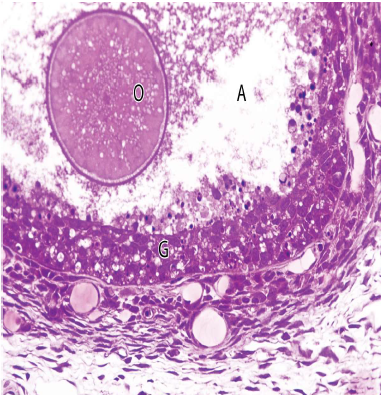

不成熟者靠外圍,較小

- follicle cells 包圍 只有一層 Simple squamous

- Simple cuboid 包圍

- 多層稱為 Stratum granulosum (顆粒層),細胞改稱 Granulosa cell

- Zona pellucida (透明帶)

- Cortical granules

- 精子進入後釋放激素,引發cortical reaction,破壞 zona pellucida 上的受體

- 出現空隙

Theca internal (TI)

- Theca external (TE)

- Cumulus oophorus (CO)

- Corona radiata (CR)